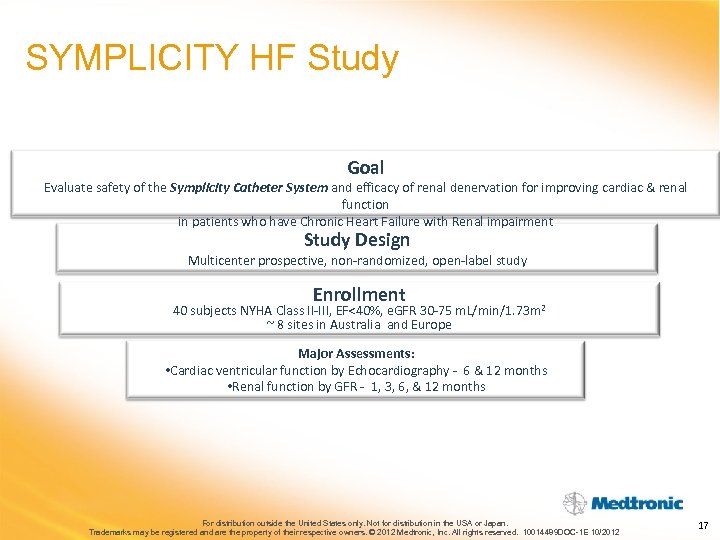

SYMPLICITY HF Study Goal Evaluate safety of the Symplicity Catheter System and efficacy of renal denervation for improving cardiac & renal function in patients who have Chronic Heart Failure with Renal impairment Study Design Multicenter prospective, non-randomized, open-label study Enrollment 40 subjects NYHA Class II-III, EF<40%, e. GFR 30 -75 m. L/min/1. 73 m 2 ~ 8 sites in Australia and Europe Major Assessments: • Cardiac ventricular function by Echocardiography - 6 & 12 months • Renal function by GFR - 1, 3, 6, & 12 months For distribution outside the United States only. Not for distribution in the USA or Japan. Trademarks may be registered and are the property of their respective owners. © 2012 Medtronic, Inc. All rights reserved. 10014489 DOC-1 E 10/2012 17

SYMPLICITY HF Study Goal Evaluate safety of the Symplicity Catheter System and efficacy of renal denervation for improving cardiac & renal function in patients who have Chronic Heart Failure with Renal impairment Study Design Multicenter prospective, non-randomized, open-label study Enrollment 40 subjects NYHA Class II-III, EF<40%, e. GFR 30 -75 m. L/min/1. 73 m 2 ~ 8 sites in Australia and Europe Major Assessments: • Cardiac ventricular function by Echocardiography - 6 & 12 months • Renal function by GFR - 1, 3, 6, & 12 months For distribution outside the United States only. Not for distribution in the USA or Japan. Trademarks may be registered and are the property of their respective owners. © 2012 Medtronic, Inc. All rights reserved. 10014489 DOC-1 E 10/2012 17